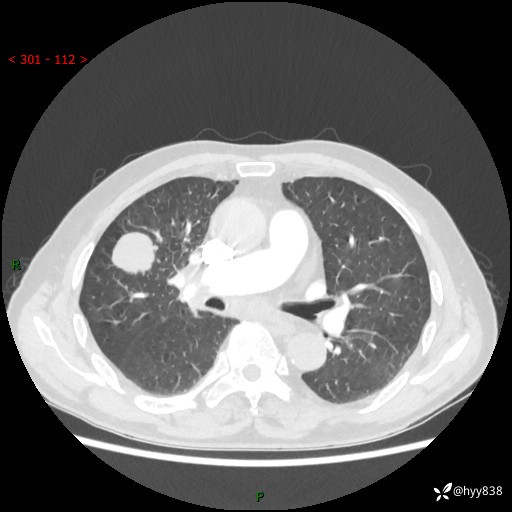

69岁/男,间断咳嗽伴气促、下肢水肿。临床拟诊肺栓,偶发肺均质强化结节--结果公布

【患者信息】:69岁/男

【主诉】:间断咳嗽伴气促、下肢水肿2周

【现病史及既往史】:患者2周来无明显诱因出现咳嗽,咳少量白痰,不易咳出,伴有气促,呈间断发作,症状与活动费力相关,以夜间为甚,不能平躺入睡,偶有憋醒,无胸闷胸痛、无发热、无头晕、头痛等不适,伴有双下肢中度水肿,就诊于当地县人民医院门诊,完善相关检查提示:左下肢深静脉血栓形成,未予以特殊处理,今患者为求进一步诊治来我院就诊,拟“心衰”收入我科。 起病以来,患者精神、饮食、睡眠可,大小便如常,体力明显下降,体重未见明显减轻。

【检查】:胸部CT增强